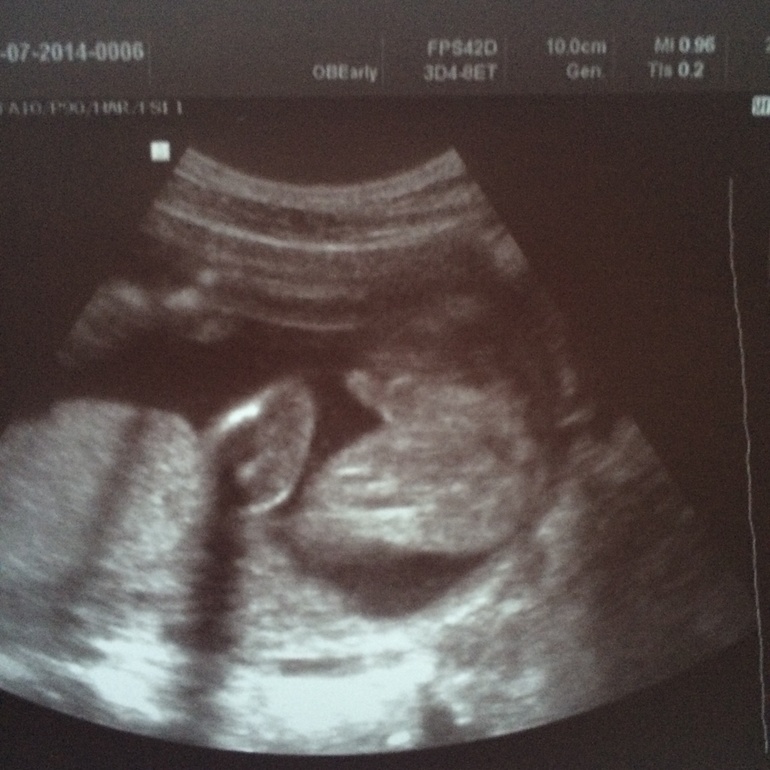

а на этой в 26 неделек,лягушоночек,попка моя сладкая и "нечто"между ножек.Это мужчина??)

в каком именно?На верхнем в левом углу только ножки,как знак "равно",и между ножек выпуклость,а на нижнем только попка(прям четко две ягодички) с согнутыми ножками и висящим между ними "нечто")

Мальчик )) ну по крайне-менее у моих именно это показывали (как на фото в 26 недель)